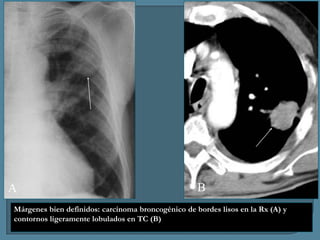

Márgenes bien definidos: carcinoma broncogénico de bordes lisos en la Rx (A) y

contornos ligeramente lobulados en TC (B)